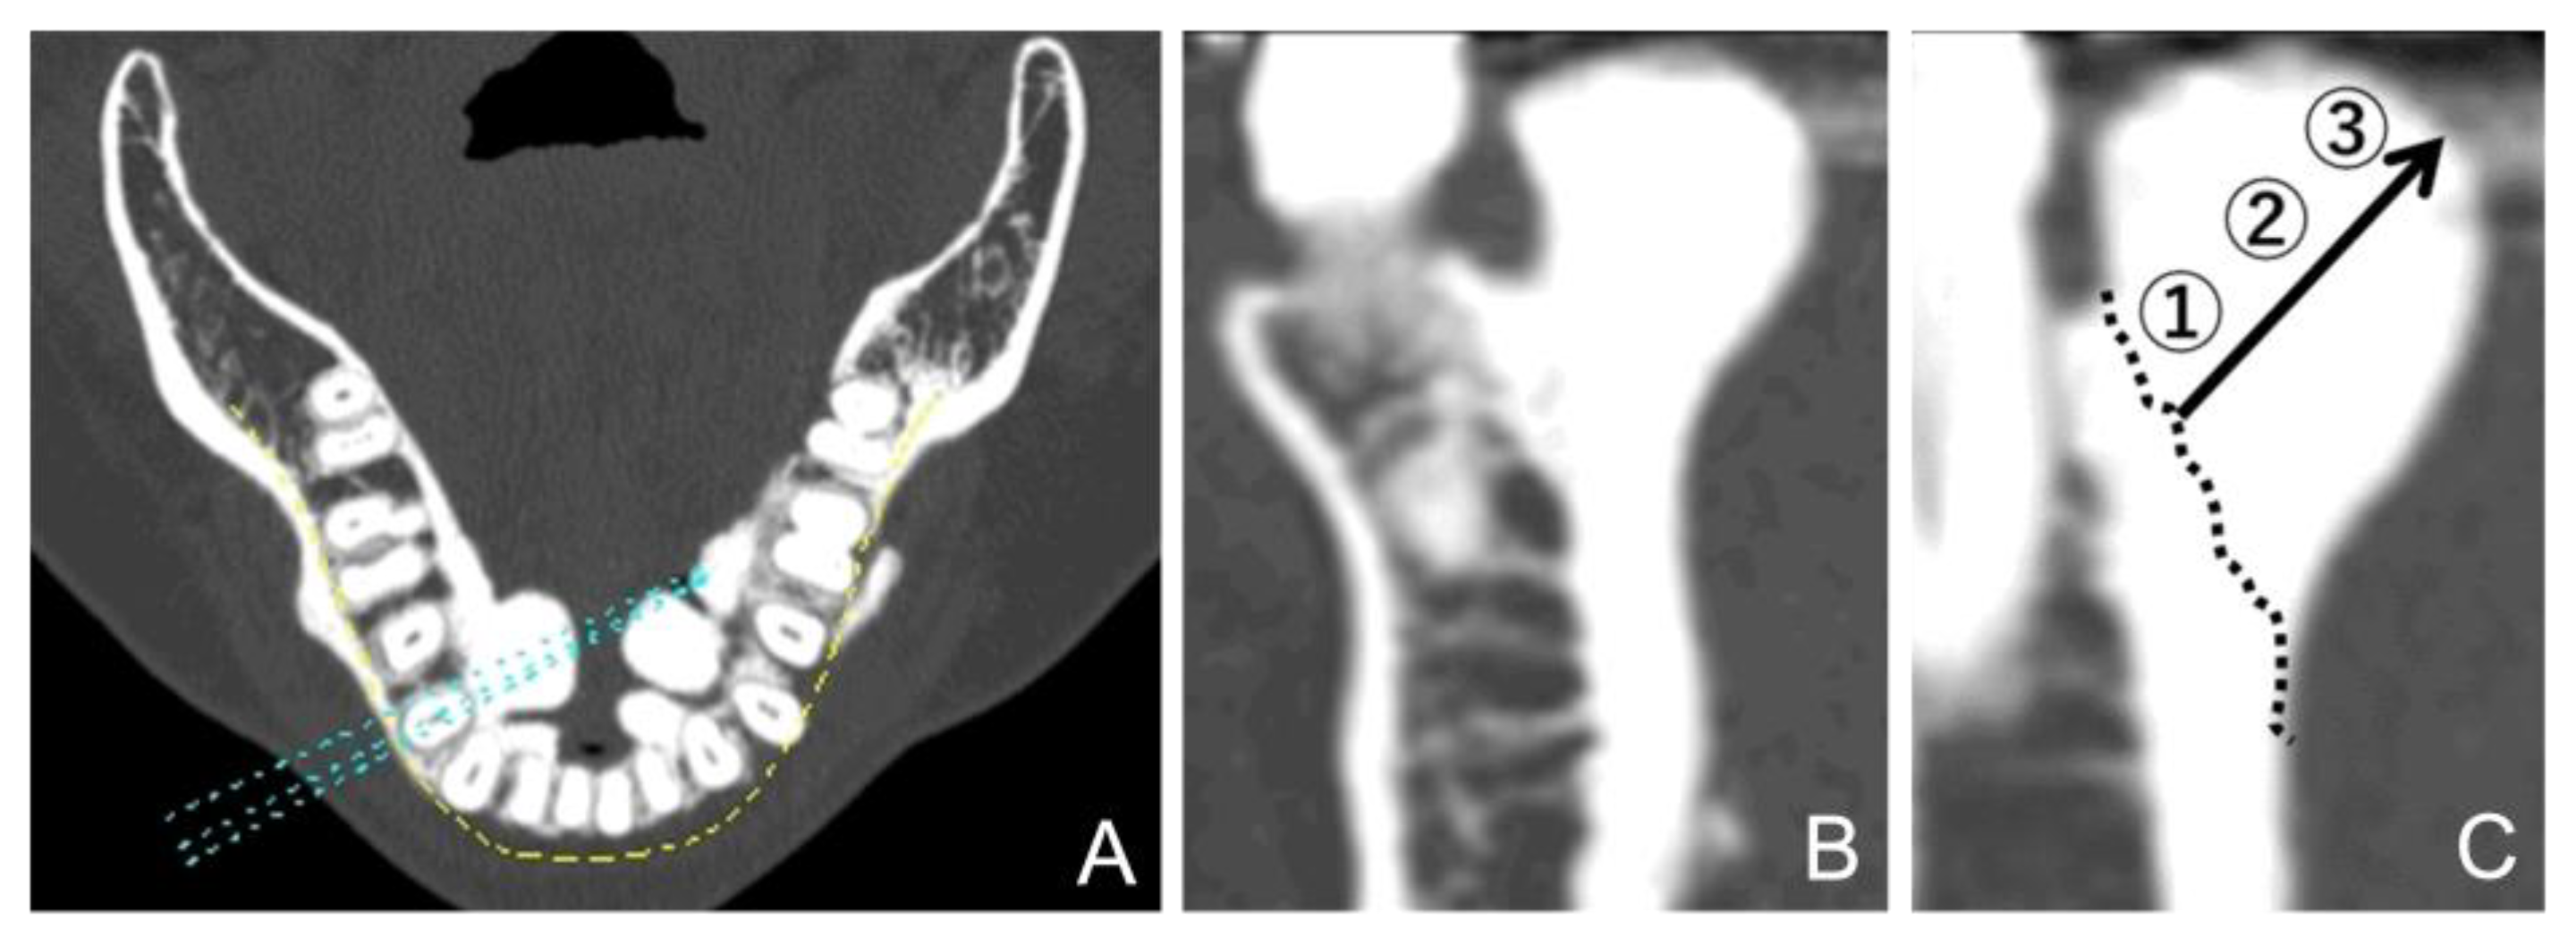

The CT value of the mandibular torus was the mean of the CT values measured at the base, center, and top of the bone (Figure 4). Three points on the cortical bone, without any obvious bulging, were arbitrarily selected and measured, with the mean of these values was used as the control value. The apical positions of the teeth were demarcated on the cross-sectional plane to provide a reference for the vertical position of the tori. The bone on the coronal side of this line was considered the alveolar bone, and the bone on the apical side was considered the mandibular bone.

Figure 4. Computed tomography (CT) value calculation of mandibular tori. (A) A panoramic curve set in the horizontal section of the CT image. (B) A cross-sectional surface in the vertical direction. (C) After setting the boundaries of the expected anatomical cortical bone (dotted line), three areas were defined: 1: The base area, 2: the central area, and 3: the maximum bulge area.